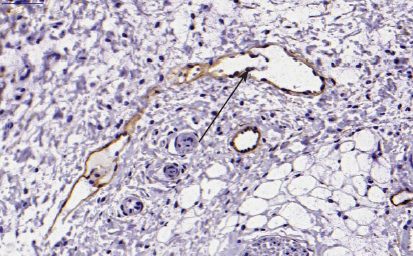

Lymphatic capillaries are thinwalled vessels that are composed of a single layer of lymphatic endothelial cells (LECs). These tiny vessels are only 30 to 80 µm in diameter, are not surrounded by pericytes or smooth muscles cells, and usually lack a basement membrane (Fig. 4-3). Lymphatic capillaries are discontinuous and contain gaps that make them highly permeable. This allows macromolecules and leukocytes to easily enter the vasculature. As lymph transits through the lymphatic capillaries, the fluid moves into precollector vessels. Unlike the capillaries, these vessels have some incomplete coverage by smooth muscle cells. The fluid then moves from precollector vessels to collecting lymphatics, which are larger vessels covered by smooth muscle cells that contain a basement membrane (see Fig. 4-3).